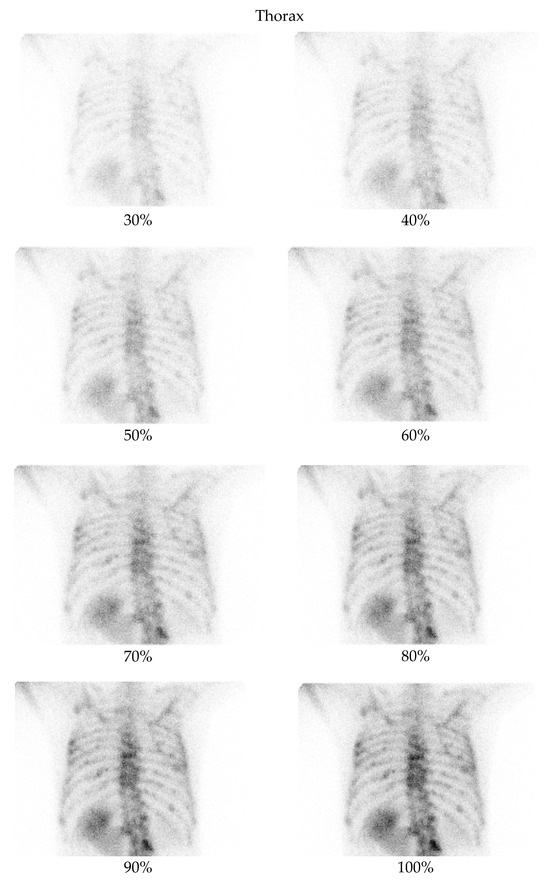

3.2. Qualitative Evaluation

- Thorax at a 70% dose: 81% of comparisons favored the denoised image.